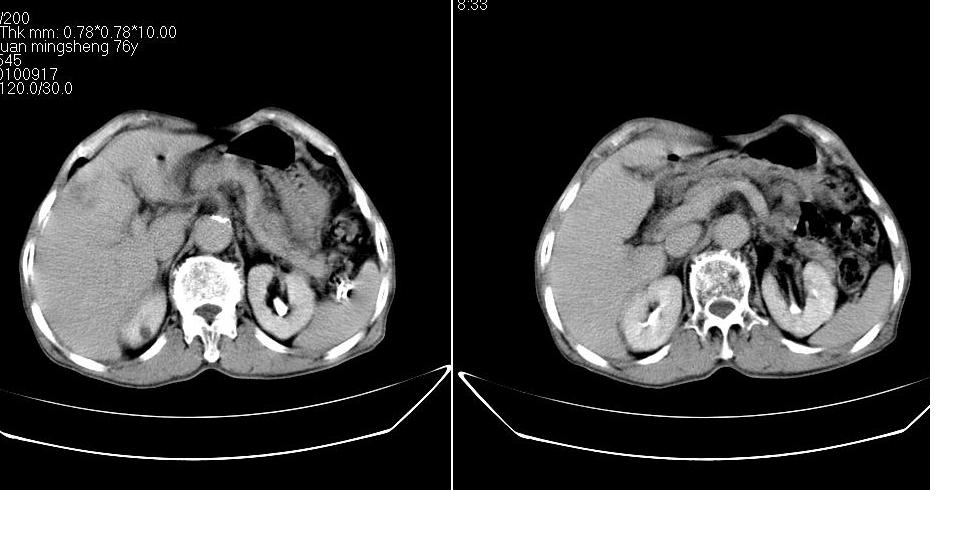

男,76岁,上腹部疼二天来就诊,彩超提示肝左叶占位,随后做上腹部ct平扫,今天做上腹部ct增强扫描,手工推药,效果不好,请谅解。

肝左叶s4肿块强化形式大概是:慢进慢出,逐渐强化----考虑血管瘤/腺瘤?{动脉期应更提前扫}。

1)肝右叶前段低密度灶,不排除肝癌可能;建议查afp。2)右肾上极囊肿。

肝内胆管积气扩张,胆囊增大,肝右前叶低密度灶,逐渐强化,一元论,胆系感染,局限性肝脓肿;右肾囊肿。

考虑肝s4段肝脓肿可能?未排除肝癌。右肾上极囊肿。